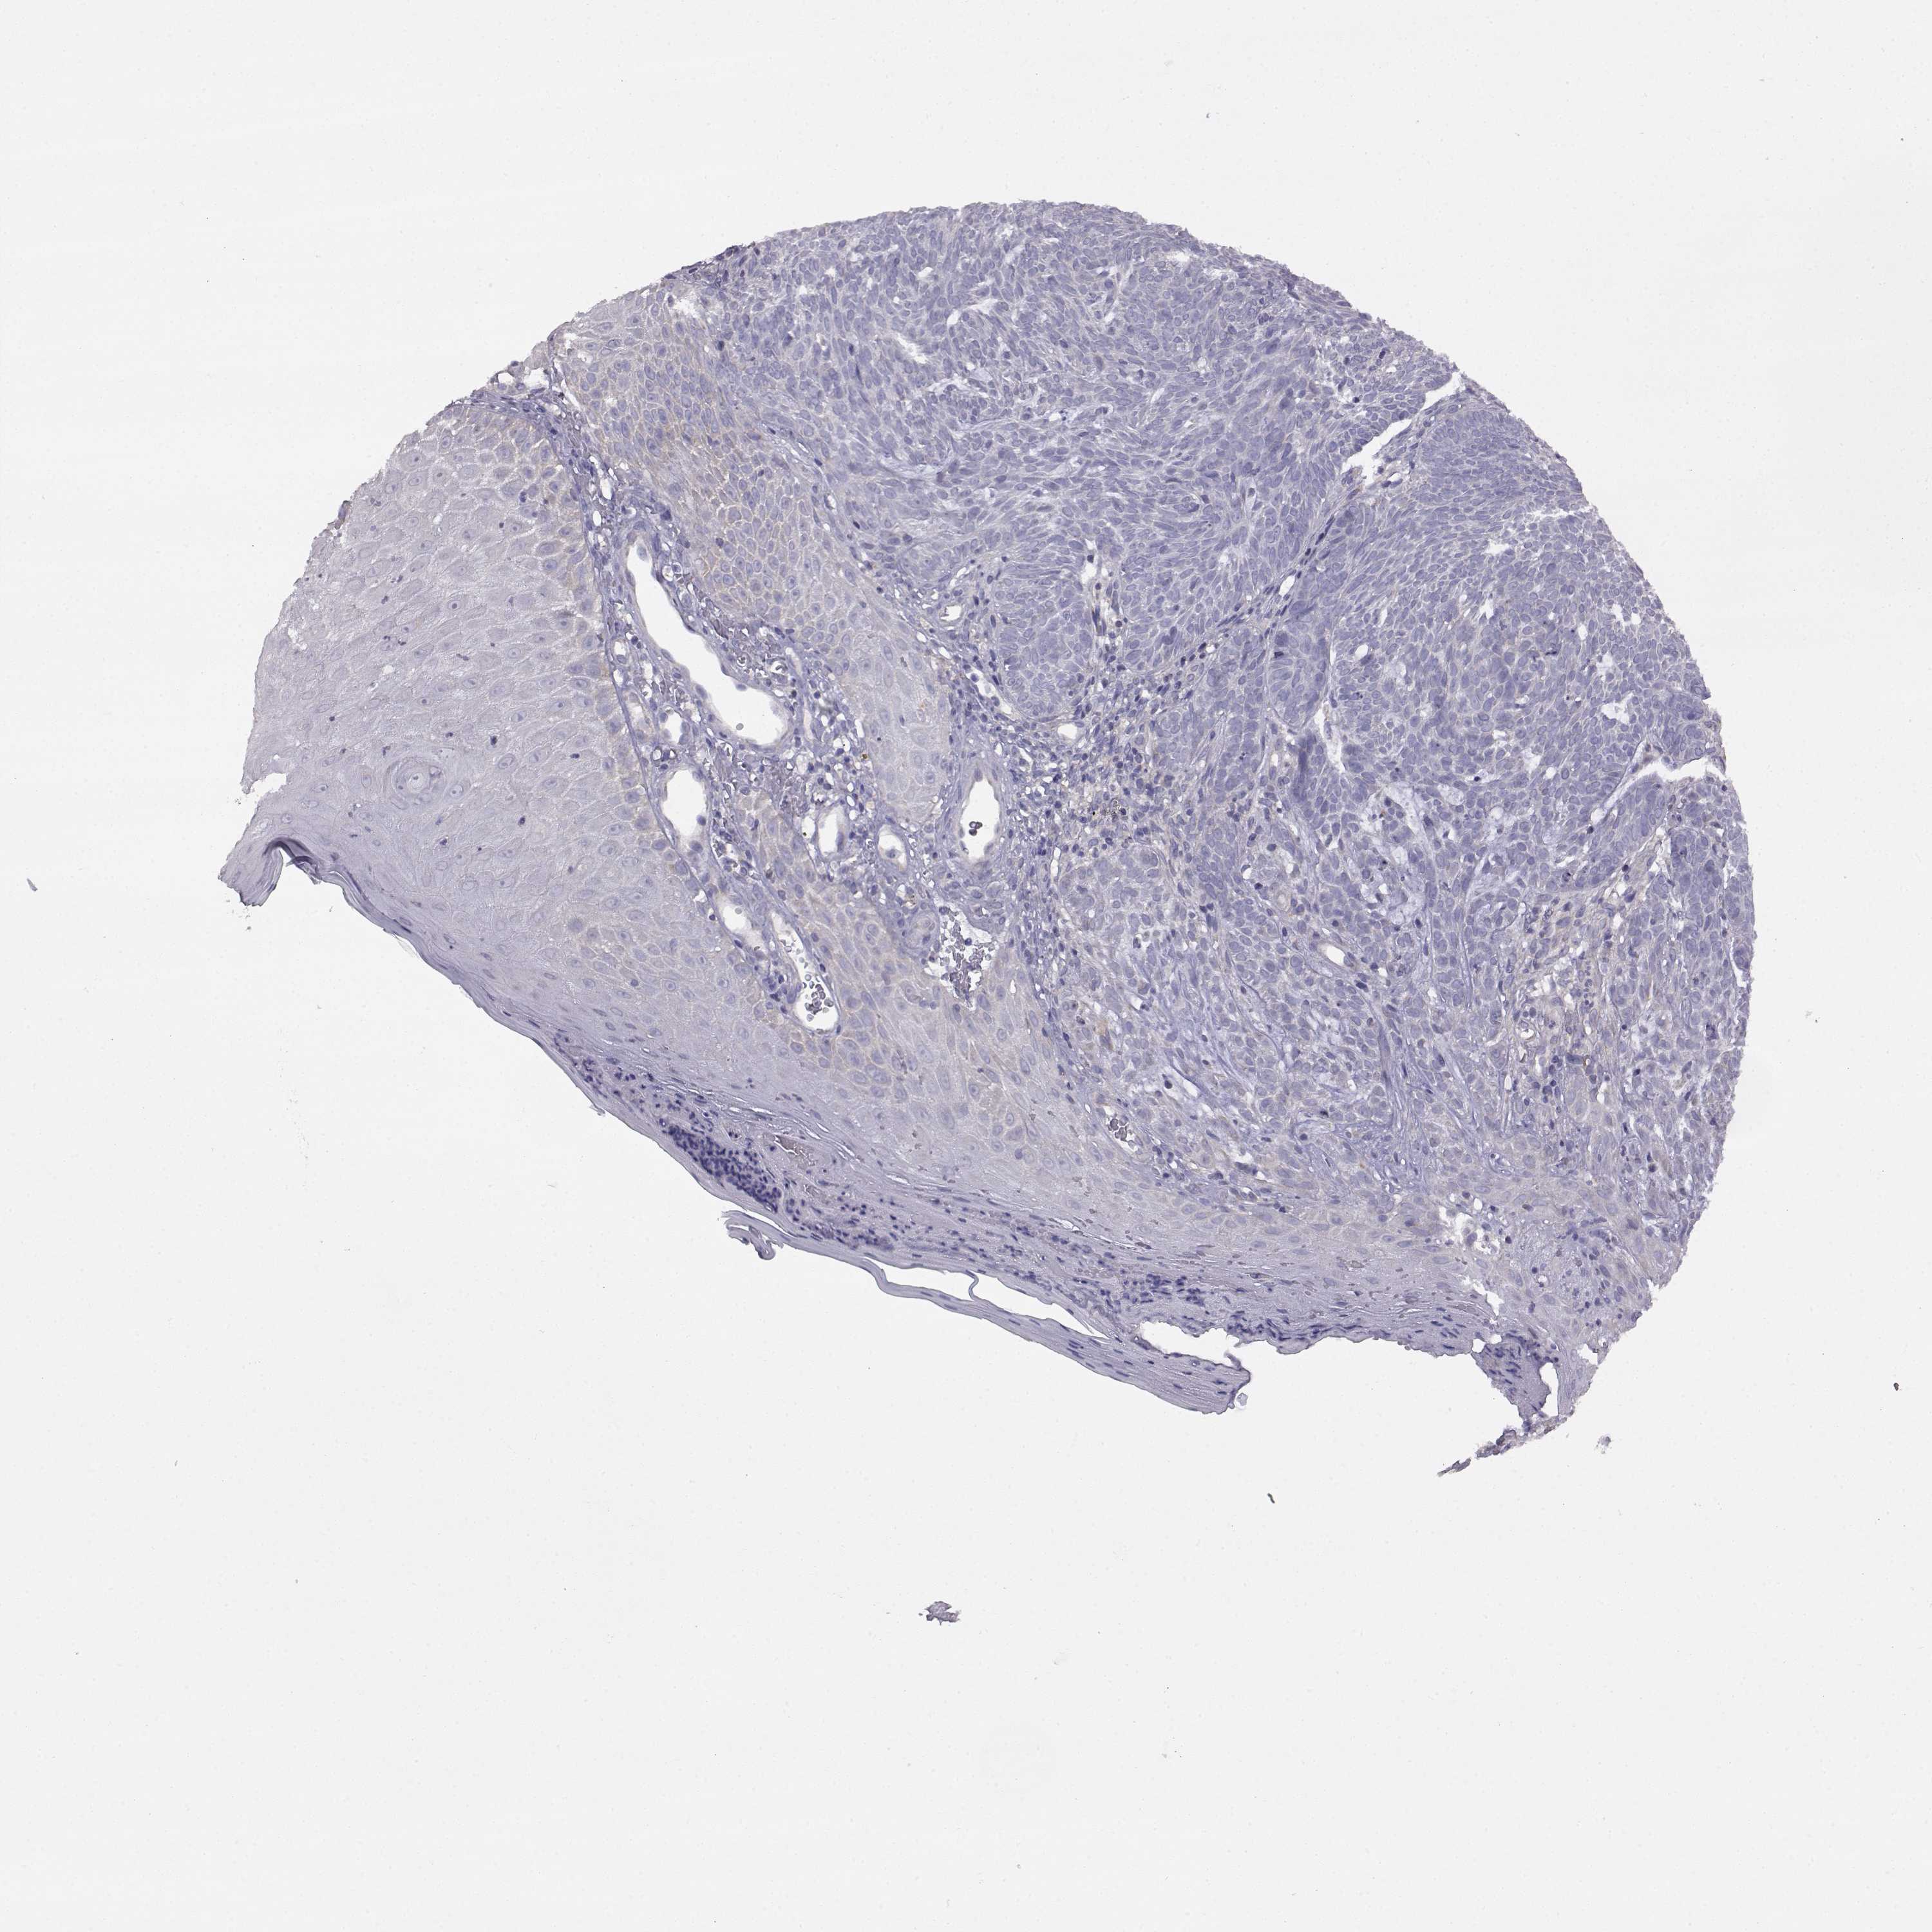

Basal cell and squamous cell cancer

SKIN CANCER - Protein expressioni

A mouse-over function shows sample information and annotation data. Click on an image to view it in a full screen mode. Samples can be filtered based on level of antibody staining by selecting one or several of the following categories: high, medium, low and not detected. The assay and annotation is described here.

Each image is clickable and will lead to virtual microscopy that enables deeper exploration of all samples and also displays staining intensity scores, fraction scores and subcellular localization as well as patient and tissue information for each sample.

Antibody HPA017742

Basal cell carcinoma

Squamous cell carcinoma, NOS